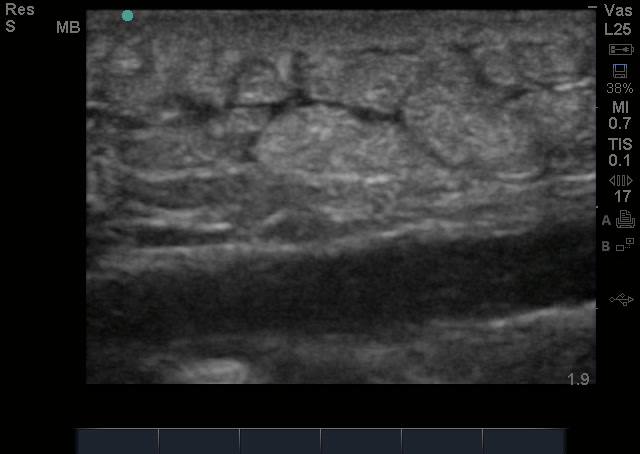

Cellulitis by bedside ultrasound looks like a bunch of rocks bunched up next to each other – termed the cobblestoning appearance of cellulitis without movement in between. If there is an abscess, this pressure will make the pus within the tissue move around, which helps in diagnosing an abscess – We call it Pus-stalsis. If there are loculations, it can easily be mistaken for cellulitis as the loculations will have echogenicity (brightness) and may look like cobblestoning, but instead, loculations are more of a cluster of grapes appearance with small movements of pus in between the loculations.

The below image shows cellulitis cobblestoning, but also more of a cluster of grapes appearance to suggest loculations. There was no compression done to evaluate whether the dark areas have “pus-stalsis” but I sure would want to….